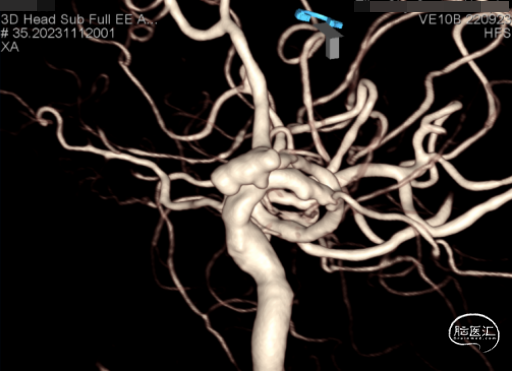

脑血管造影及3D重建示前交通动脉瘤,大小约7.6*5.2*4.8mm,瘤颈宽3.8mm,3个子瘤分别朝向不同方向,瘤颈处子瘤朝向对侧上方,考虑为动脉瘤破裂处。